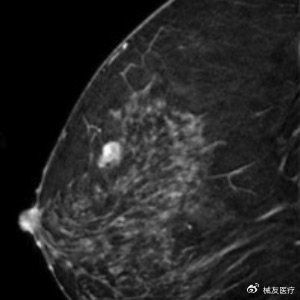

这款产品确实很有来头。它采用低频声波技术,能做3D乳腺成像,而且无辐射、无痛,被寄予厚望要挑战传统钼靶的“金标准”地位。正因为技术过硬,公司还拿到了美国国立卫生研究院1550万美元的资助。

它的核心技术QTscan,可以理解为超声检查的"升级版"。传统超声检查很依赖医生的手法,不同医生做出来的结果可能差别很大。而QTscan通过旋转发射器,实现多角度信号采集,生成3D容积图像,不仅信息量更丰富,还实现了标准化操作,每个乳腺检查只要10分钟。

更关键的是,这项技术特别适合中国女性。因为中国女性多为致密型乳腺,传统钼靶检查就像在浓雾里找人,准确率大打折扣。而超声检查对致密乳腺更敏感,正好弥补了这个缺陷。